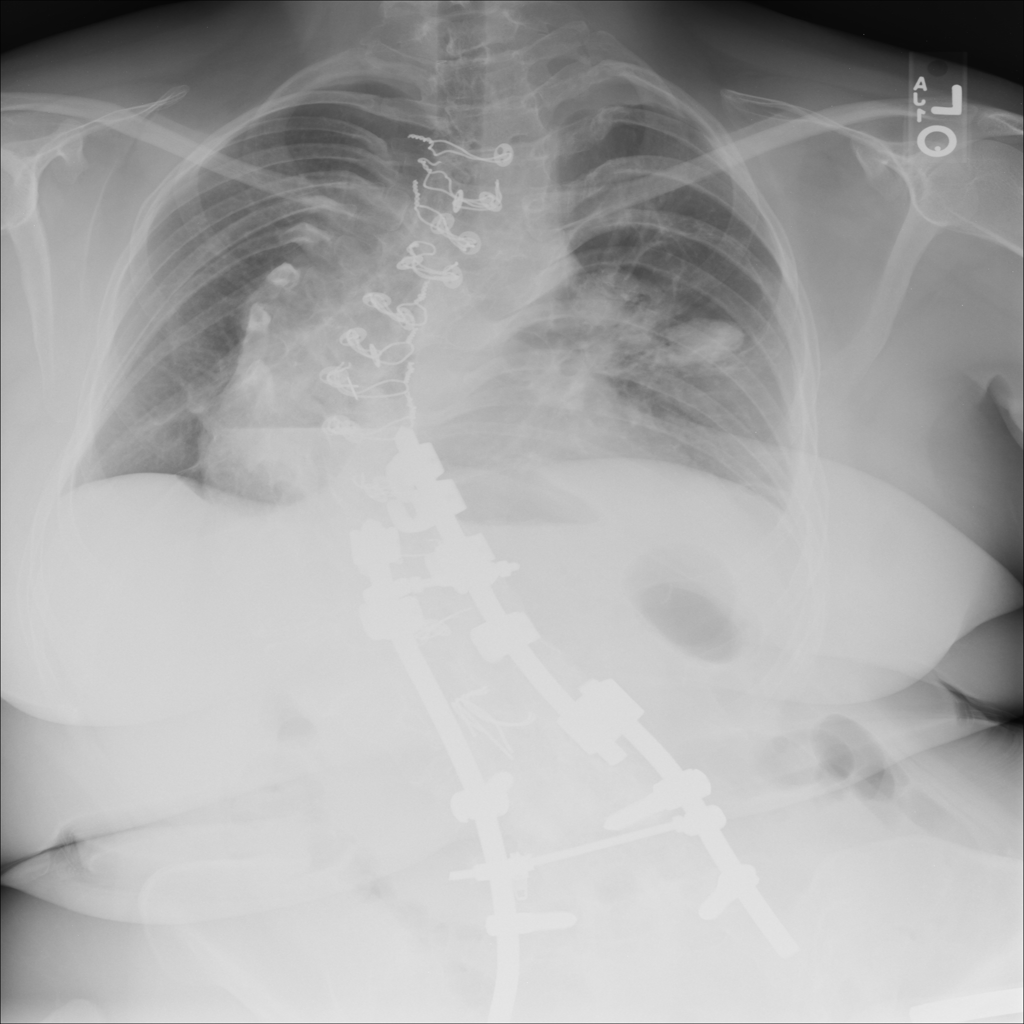

PAT-4639 · IMG-024Mass

PAT-4639 · IMG-024

AP